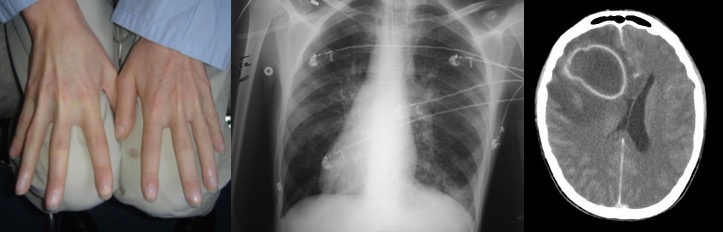

- les abcès d’origine hématogène : ils surviennent dans un contexte connu de cardiopathie cyanogène (devenue un cause rare d’abcès en raison des progrès de la chirurgie cardiaque), une fistule artérioveineuse pulmonaire (syndrome de Rendu-Osler) ou une infection bronchique chronique comme dans le syndrome de Kartagener.

elle consiste au minimum en une ponction de l’abcès, par trépanation, éventuellement guidée par neuronavigation, ou par ponction trans-fontanellaire éventuellement sous contrôle échographique. il s’agit le plus souvent d’une urgence chirurgicale en raison du risque d’aggravation rapide au plan neurologique comme au plan infectieux.

en pédiatrie, on note cependant que plus de la moitié des patients nécessitent une craniotomie, en raison :

- d’une récidive rapide après ponction

- d’une topographie peu accessible à la ponction

- d’un diagnostic erroné (tumeur)

pour fermeture de la porte d’entrée

au total, de nombreux patients nécessitent plus d’une intervention (ci-contre).